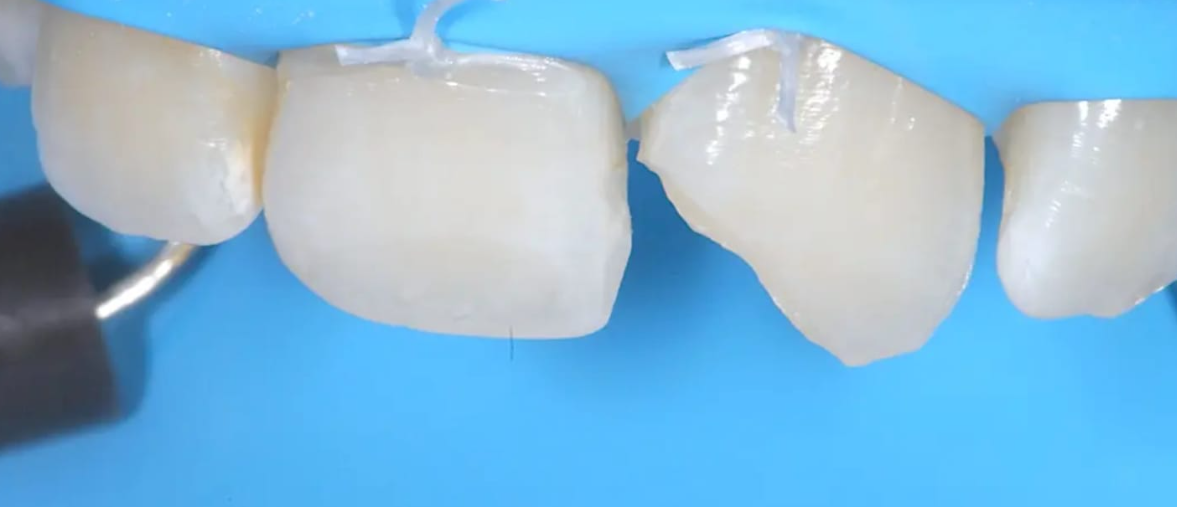

Restaurar un diente individual con una corona o un relleno.

El dentista evalúa la boca y determina el mejor plan de tratamiento para la reconstrucción dental, también crea un plan de tratamiento personalizado para restaurar la forma y la función de los dientes y la boca.

El dentista realiza el tratamiento de reconstrucción dental, que puede incluir la colocación de prótesis dentales, implantes dentales, coronas, puentes y otros tratamientos, luego el dentista realiza un seguimiento para asegurarse de que la reconstrucción dental sea exitosa y de que la boca esté saludable.